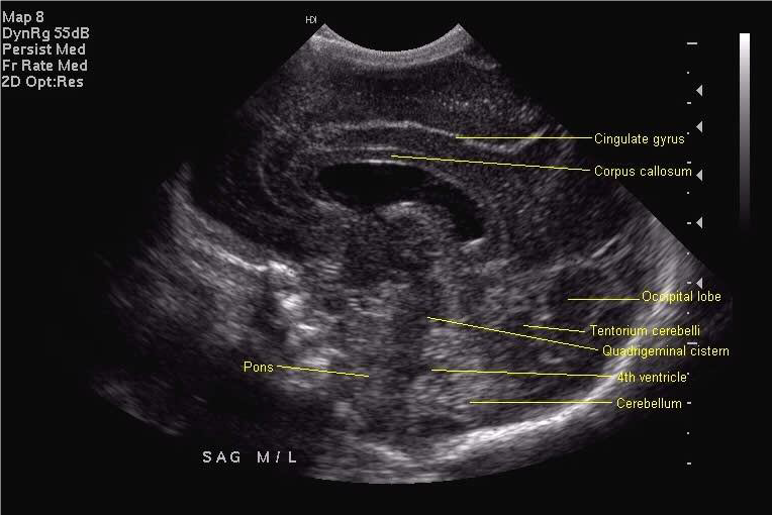

Standard views for cranial ultrasonography of the newborn

Midline Sagittal